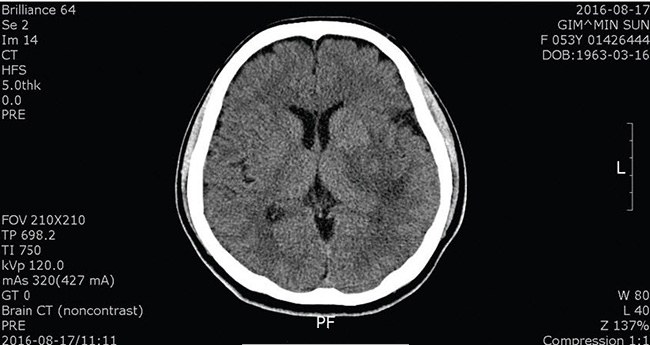

On July 31, 2016, I felt drained of energy. I felt a little numb on the right side of my body. I did not have time to check it out in hospital then. So, at 11 P.M. on the next day, I went to the emergency room of Boramae Hospital. The doctor performed a CT scan, and it revealed a cerebral hemorrhage.

On August 8, I participated in Manmin Summer Retreat. I received Senior Pastor’s prayer with faith during the seminar of the first day. On August 17, I had a CT scan done again. The doctor said blood had been soaked up, and all body functions were mysteriously normal. Hallelujah!